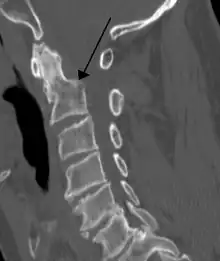

Fractures of the dens, not to be confused with Hangman's fractures, are classified into three categories according to the Anderson Alonso system:

- Type I fracture - Extends through the tip of the dens. This type is usually stable.

- Type II fracture - Extends through the base of the dens. It is the most commonly encountered fracture for this region of the axis. This type is unstable and has a high rate of non-union.

- Type III fracture - Extends through the vertebral body of the axis. This type can be stable or unstable and may require surgery.

Type 3 odontoid fracture